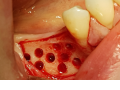

Augmentacja boczna wąskich wyrostków zębodołowych z…

Damian Dudek, Maciej Jagielak, Aldona Chloupek, Oliwia Warmusz, Edyta Reichman-Warmusz